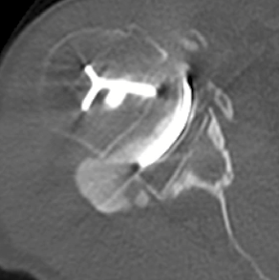

CT scan confirmed glenoid loosening with severe osteolysis and evidence of component rocking in the superior and posterior direction.